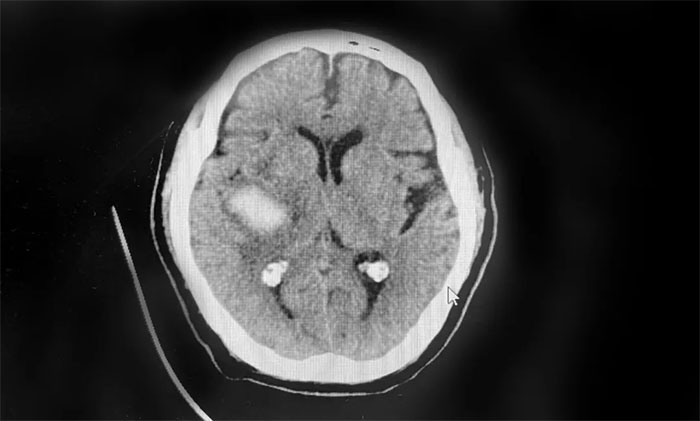

深化学术交流,精进诊疗能力 | 2025年“蓝十字大讲堂”第八期开讲 聚焦韦尼克脑病诊治